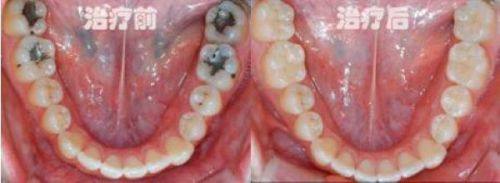

牙齿修复:涵盖烤瓷牙、树脂补牙等多种修复项目,医师会根据患者牙齿缺损情况定制个性化方案,修复后牙齿外观自然逼真,能修复正常咀嚼功能。